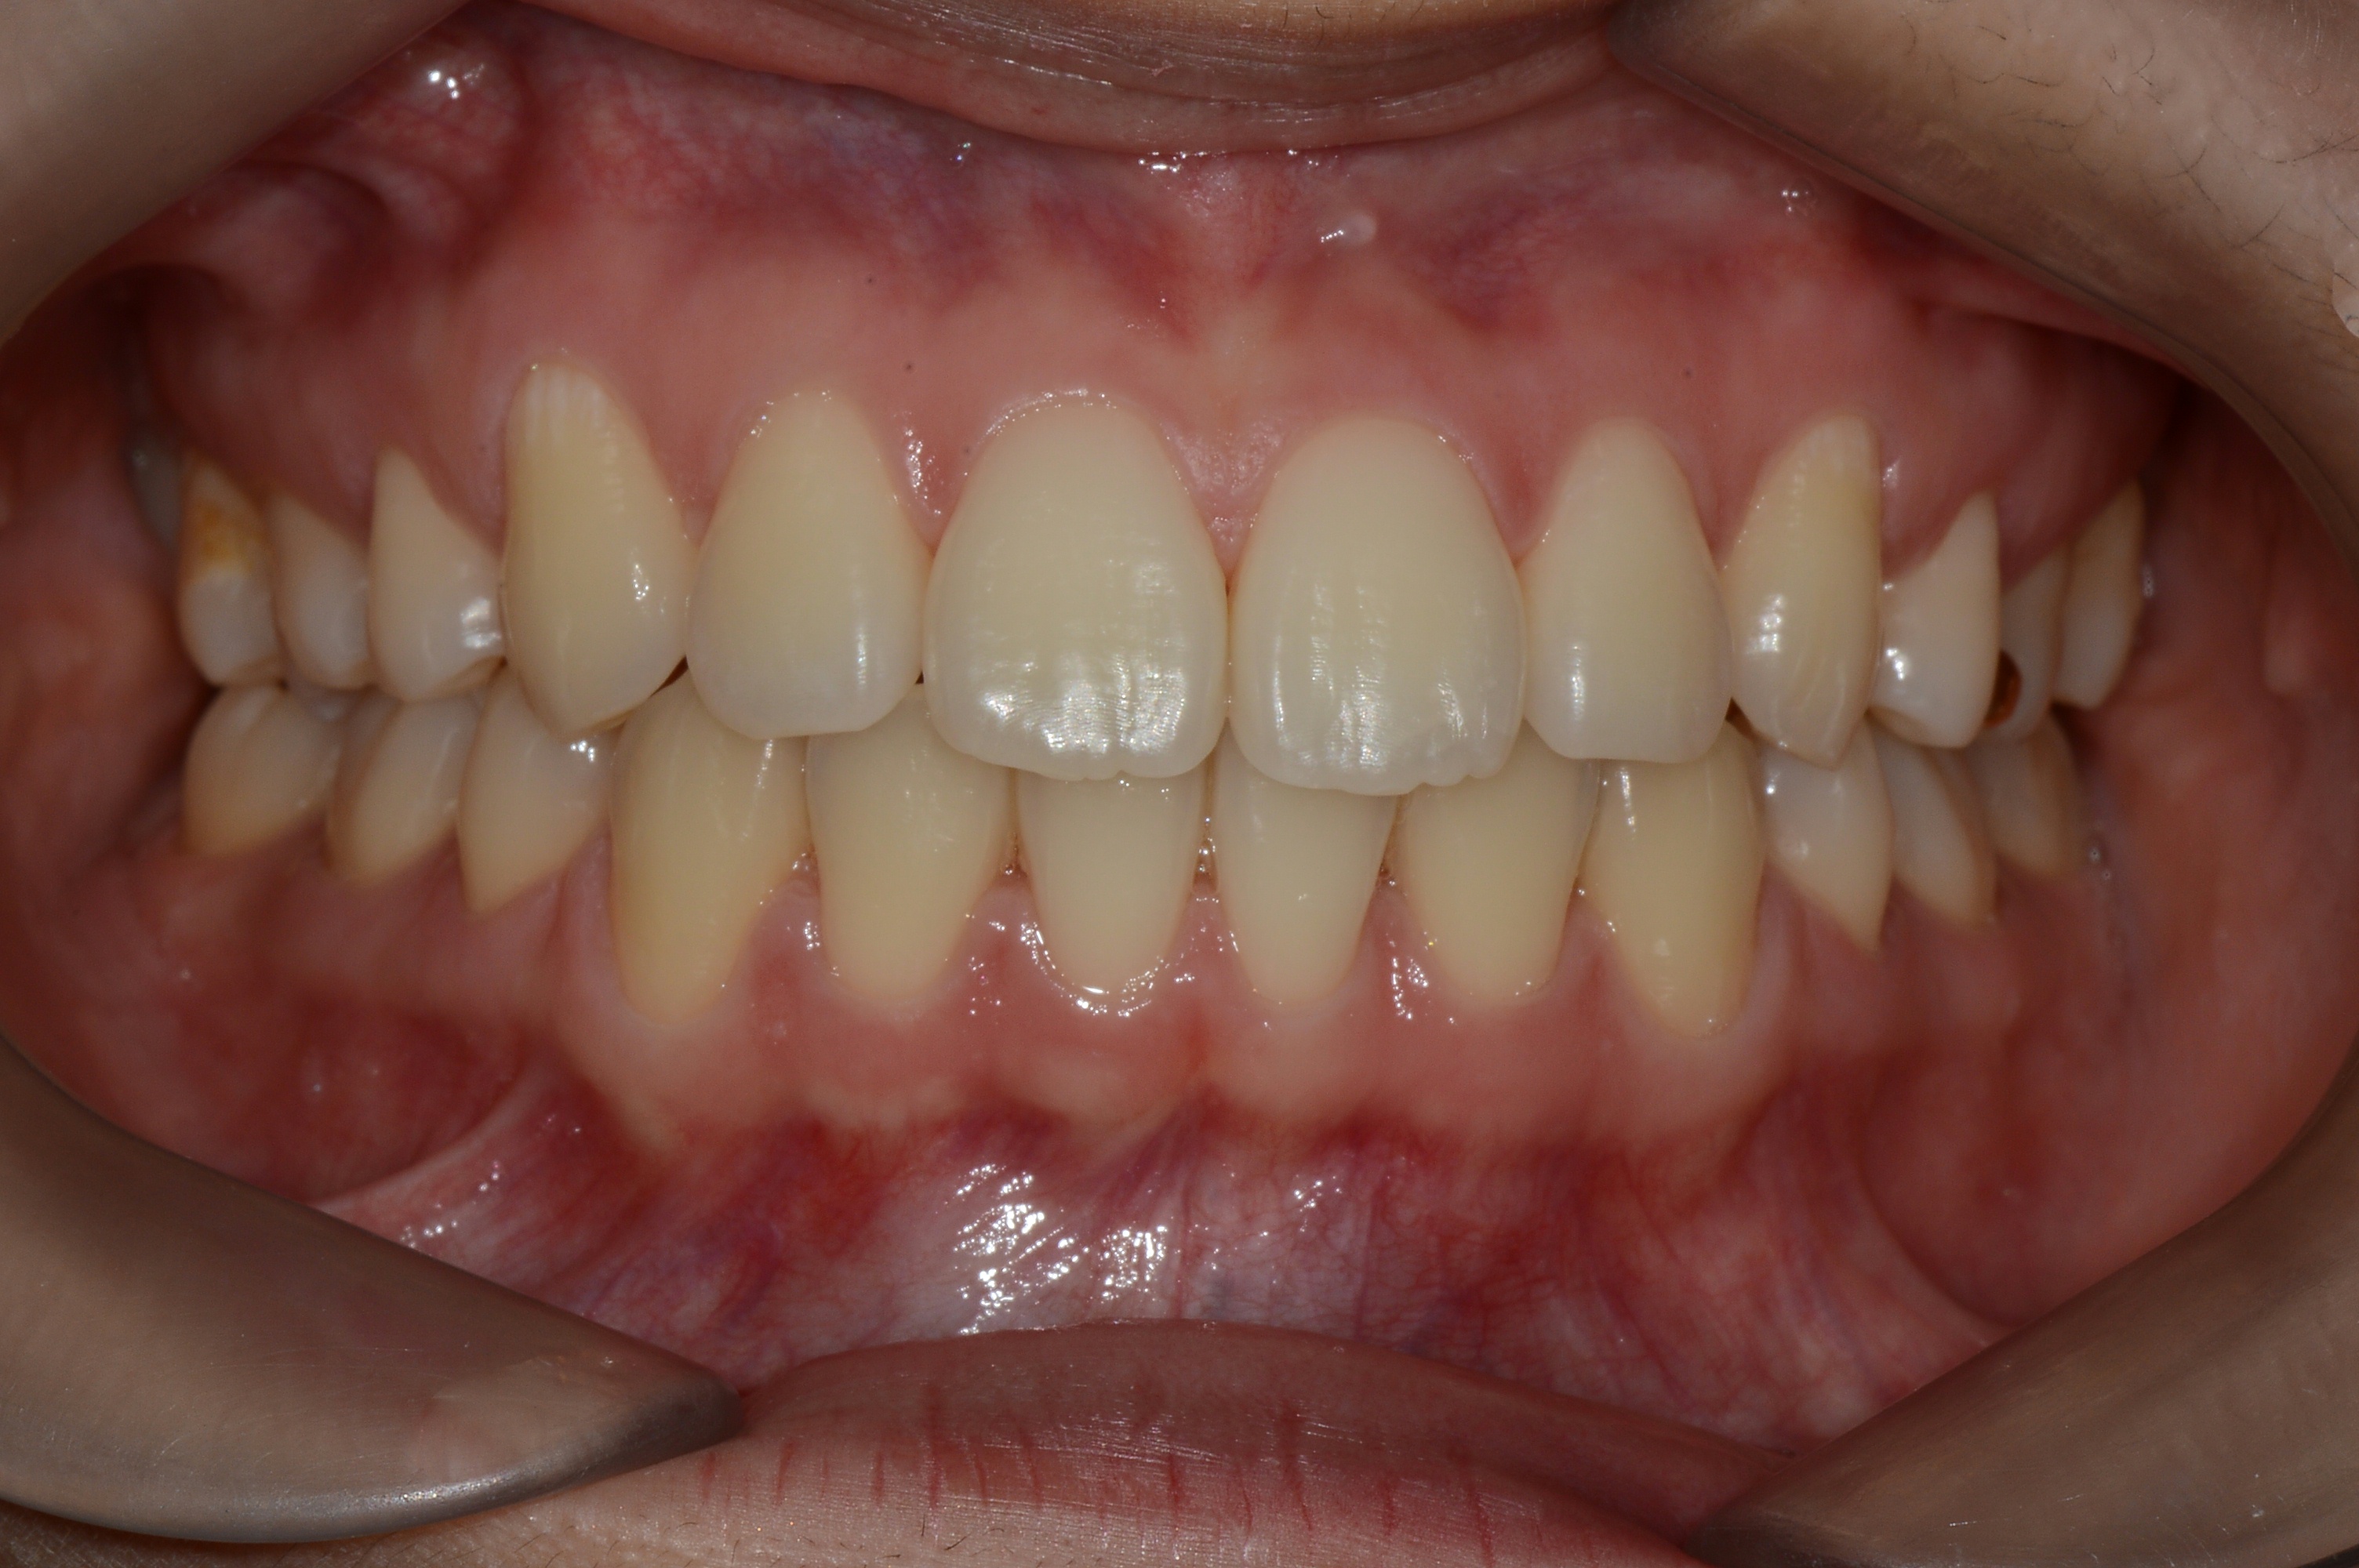

치료 후 사진입니다.